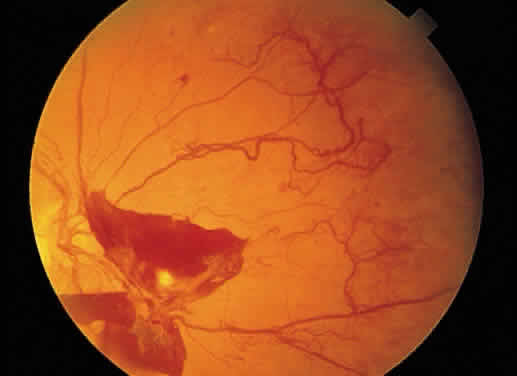

RED CHANGES IN THE FUNDUS Red lesions in the fundus indicate the presence of blood or abnormal blood

vessels in an abnormal location. The blood may be intravascular, implying

a vascular pathologic process, or extravascular, as in hemorrhage. Microaneurysms, such as those seen in diabetic retinopathy (Fig. 52), are reflective of vascular abnormality, which has been demonstrated

histologically using trypsin-digestion techniques (Fig. 53). Notice that many microaneurysms measure less than 60 μm in diameter. Since

the maximum resolving power of the direct ophthalmoscope is 60 μm, many

of the small red dots observed in the fundus are not microaneurysms

but microhemorrhages. In fact, alterations in vascular permeability

are seen early in background diabetic retinopathy, and the

microaneurysms frequently leak fluorescein during angiographic studies. Therefore, fluorescein

angiography may be a more sensitive technique

for the detection of microaneurysms than is direct fundus observation.18  Fig. 52. A. Fundus photograph of nonproliferative diabetic retinopathy. Notice the

dilated veins, the small exudate clusters, the ischemic infarct (cotton-wool

spot), and the numerous microaneurysms and small hemorrhages. B. Mid-venous phase fluorescein angiogram of the same eye. Notice the focal

area of nonperfusion in the superior temporal arcade (ischemic areas), the

fluorescing microaneurysms, and the hemorrhages, which appear

dark in contrast to the background fluorescence. (Courtesy of William Tasman, MD, Philadelphia, PA) Fig. 52. A. Fundus photograph of nonproliferative diabetic retinopathy. Notice the

dilated veins, the small exudate clusters, the ischemic infarct (cotton-wool

spot), and the numerous microaneurysms and small hemorrhages. B. Mid-venous phase fluorescein angiogram of the same eye. Notice the focal

area of nonperfusion in the superior temporal arcade (ischemic areas), the

fluorescing microaneurysms, and the hemorrhages, which appear

dark in contrast to the background fluorescence. (Courtesy of William Tasman, MD, Philadelphia, PA)

|